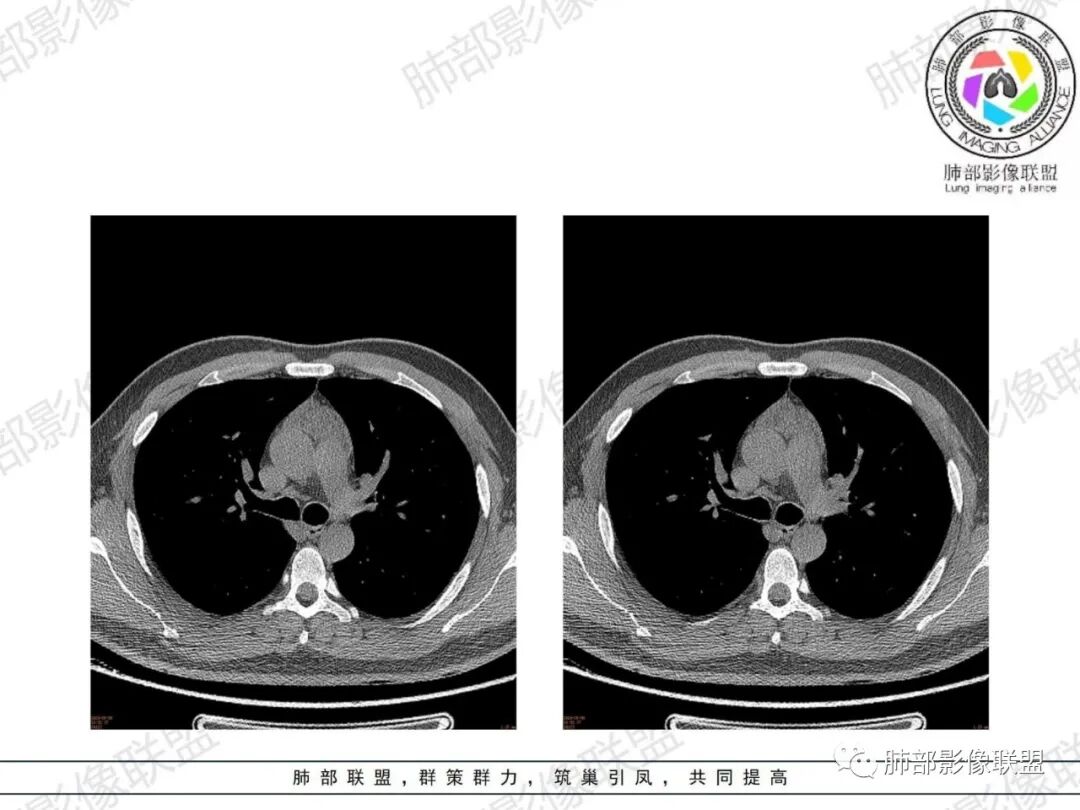

胸腺增生CT表现

体积、形态:

弥漫性增大,两缘对称,质地柔软,部分淋巴性胸腺增生的大小正常;形态保持其正常形态,呈类圆形、梨形,边缘光滑,可呈浅分叶

密度:

密度均匀,呈肌性密度,偶见细小钙化,其内有脂肪浸润样密度影

强化:

轻度或无强化

与周围结构关系:

与周围大血管、胸骨等周围组织结构分界清楚,无淋巴结肿大、胸膜及心包受累。

1、年轻男性,双下肌乏力,胸部CT提示前纵隔胸腺区病变,应当怀疑胸腺增生或胸腺瘤导致的重症肌无力。

2、前纵隔梨形软组织密度影,与正常胸腺形态一致,为胸腺弥漫性增大,两缘匀称,质地柔软,未见明显膨隆,其内可见脂肪浸润影,与周围结构分界清楚,再加上病人年龄,需要高度提示胸腺增生(淋巴滤泡样增生型)。胸腺瘤一般无脂肪浸润,质地较硬,呈结节或肿块状,且发病年龄较大。B2B3型肿块边界不清,可侵犯临近组织脏器,B3可胸膜转移,胸腺癌可引起纵隔淋巴结及远处转移。